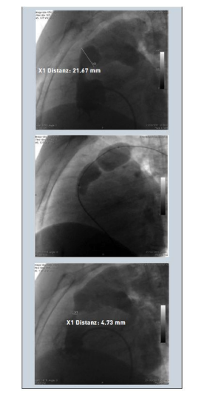

Hình: Các bước nong van động mạch phổi